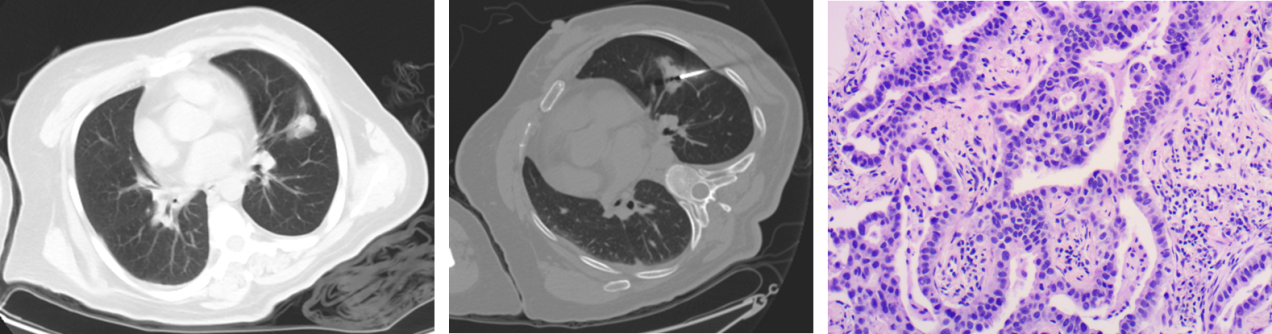

北京清华长庚医院8月27日电(通讯员  董鸿鹏)患者系老年女性,因“腰腿痛半年,加重三个月”于外院拟行腰椎间盘突出症手术治疗。术前胸片发现左肺阴影,胸部CT提示“左肺团片影,慢性炎症可能性大,占位性病变不除外,建议抗炎治疗后复查”。患者于2015年5月初来我院“影像介入门诊”就诊,放射科马永强医师阅片后考虑病变肺癌可能性大,建议穿刺活检明确诊断。征得患者及家属同意后,马永强医师为患者左肺病灶行CT引导下穿刺活检,术后病理提示“浸润性腺癌,外院PET-CT全身扫描提示“左肺上叶舌段占位,FDG摄取增高,最大SUV3.6,同时发现L5棘突骨转移,属肺癌晚期,无手术切除机会。在征得患者及家属同意后,马永强医师于2015年5月中旬为患者行肺癌射频消融术治疗,手术顺利,无并发症发生,患者术后2个月外院PET-CT复查提示:左肺肿块接近消失,仅残留少许纤维条索,FDG无摄取。治疗效果显著,患者及家属送来锦旗表示感谢。